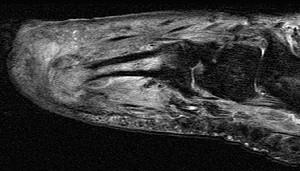

女,55岁,第3趾肿胀,结合图像,最可能的诊断是 ( )A、结核B、化脓毒性关节炎并骨髓炎C、未见异常D、骨髓炎E、化脓性关节炎

问题 女,55岁,第3趾肿胀,结合图像,最可能的诊断是 ( )

选项 A、结核 B、化脓毒性关节炎并骨髓炎 C、未见异常 D、骨髓炎 E、化脓性关节炎

答案 B